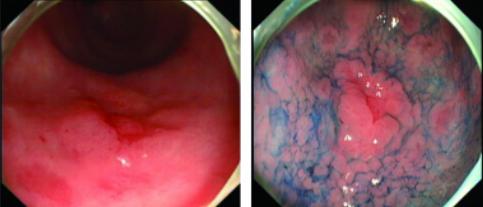

3、靛胭脂

正常消化道粘膜是光滑的,当有微小病变,如溃疡、癌变等,表面就会发生变化,但是在早期由于病变范围很小,很难在普通内镜下发现。但是当对粘膜喷洒染色剂后,表面光滑的部分,靛胭脂不能沉淀而全部沉积在粘膜皱襞的沟纹之间,与桔红色粘膜形成鲜明对比,在直视下,形成连续的线条,显示出粘膜的细微凹凸变化及其立体结构,如喷洒靛胭脂后病变边界不清,则多为炎症反应;如边界清晰,也就是内镜医师常说的“definition line”这时需要抵近观察病变部位组织细节,如有小凹形态异常,应引起注意,有条件的应使用共聚焦显微内镜仔细观察纤体及细胞形态,并应在此病变部位取活检,进行病理学诊断。